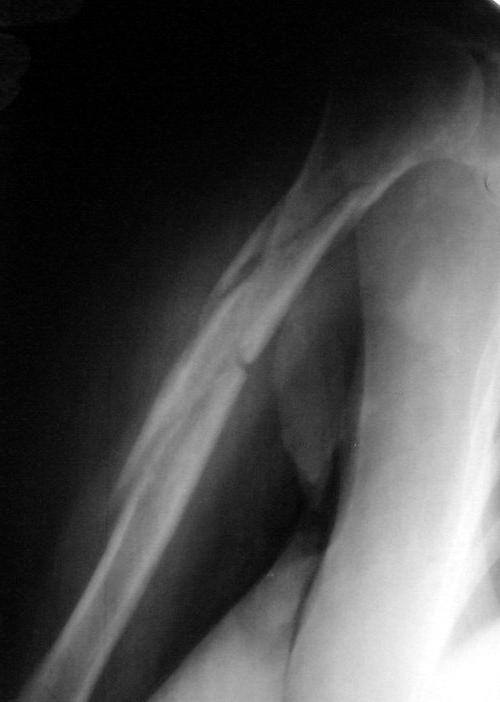

Многооскольчатый перелом плечевой кости в В/3 - ПРОДОЛЖЕНИЕ

Продолжение сообщения от 11 сентября 2007 г.

Вот результат консервативного лечения данного перелома. Консолидация достаточная, клинически подвижности нет. Занимаюсь реабилитацией. Думаю функцию плечевого сустава можно будет восстановить на 70-80%